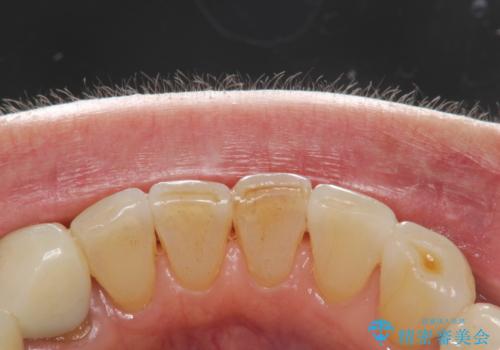

インビザライン中に歯の着色落としクリーニング PMTC

- インビザライン治療中に着色が気になるとのことでクリーニングを希望されました。PMTC30分コースを行いました。

インビザライン治療中には、歯の表面にアタッチメント(効率的に歯の移動をするもの)を設定します。そのため歯ブラシでは届きにくい細かい部分などに、歯石や着色がついてしまうことがあります。着色などを放置していると、着色なのか、虫歯なのかの判別もしずらく正確にお口の中の状態を診断できません。